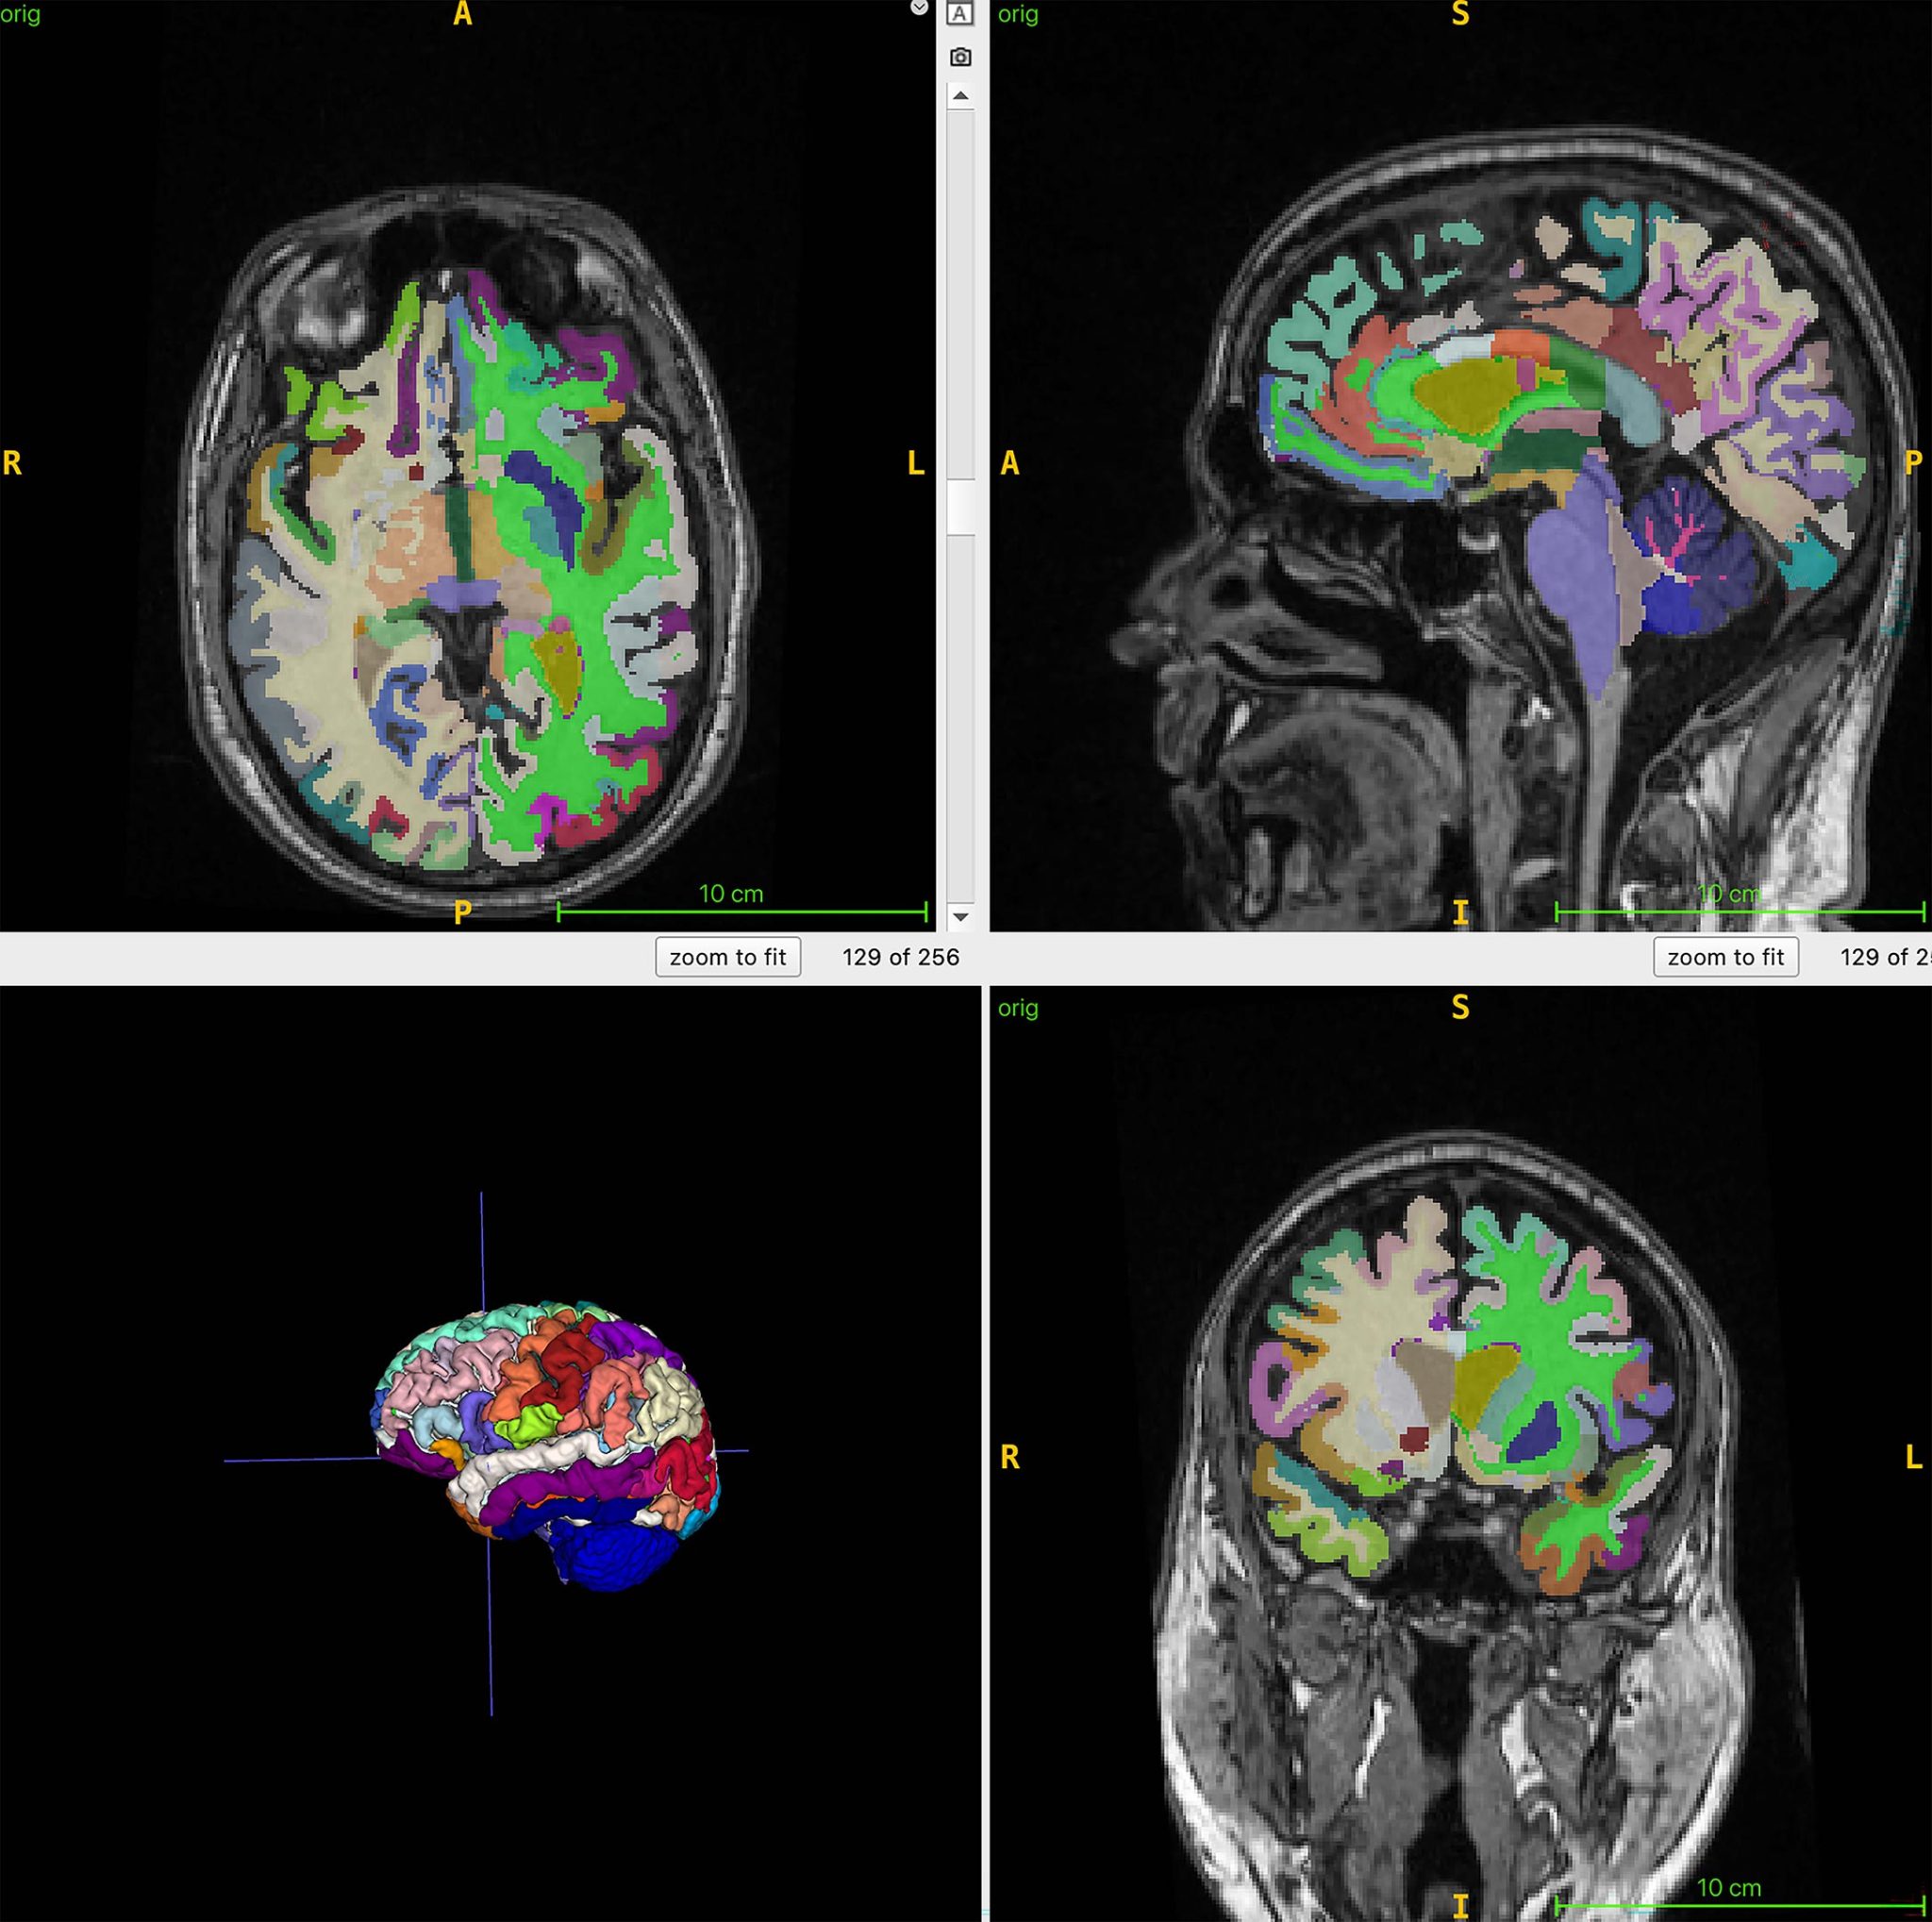

L'analyse combine des scans IRM et des outils d'intelligence artificielle pour mesurer précisément les volumes musculaires et graisseux. Les participants, d'âge moyen 55 ans, ont subi des examens d'imagerie par résonance magnétique dans plusieurs centres. Les chercheurs ont utilisé des séquences T1 pour visualiser clairement les tissus, permettant à l'IA de calculer l'âge cérébral à partir de la structure du cerveau.

Figure cérébrale en couleur montrant un exemple de volumes régionaux segmentés obtenus à partir des scans IRM volumétriques 3D T1 utilisés pour les calculs d'âge cérébral par intelligence artificielle.

Crédit: Cyrus Raji, M.D., Ph.D., et RSNA